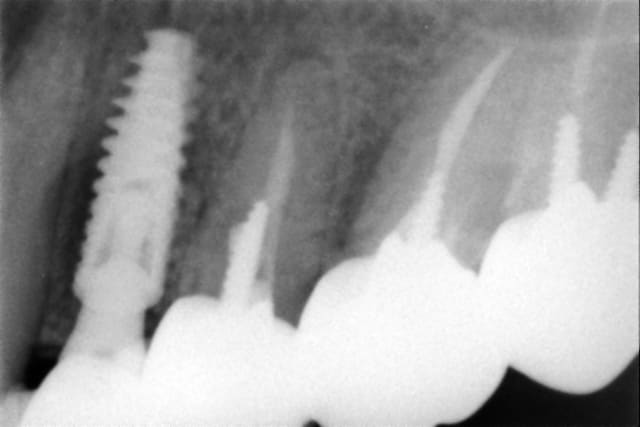

Un "vieux cas" LEONE qui se passe bien malgré des conditions de départ et de chirurgie pas au mieux! 4 ans déjà et aspect sympa très stable dans le temps. une de mes extractions implantation immédiate en site "pas idéal".La chronologie en rx.

Janvier 2008 vzunxr - Eugenol

Octobre 2008 ehmsfj - Eugenol

Mars 2008 jt5qx2 - Eugenol

Novembre 2011 ane4ar - Eugenol